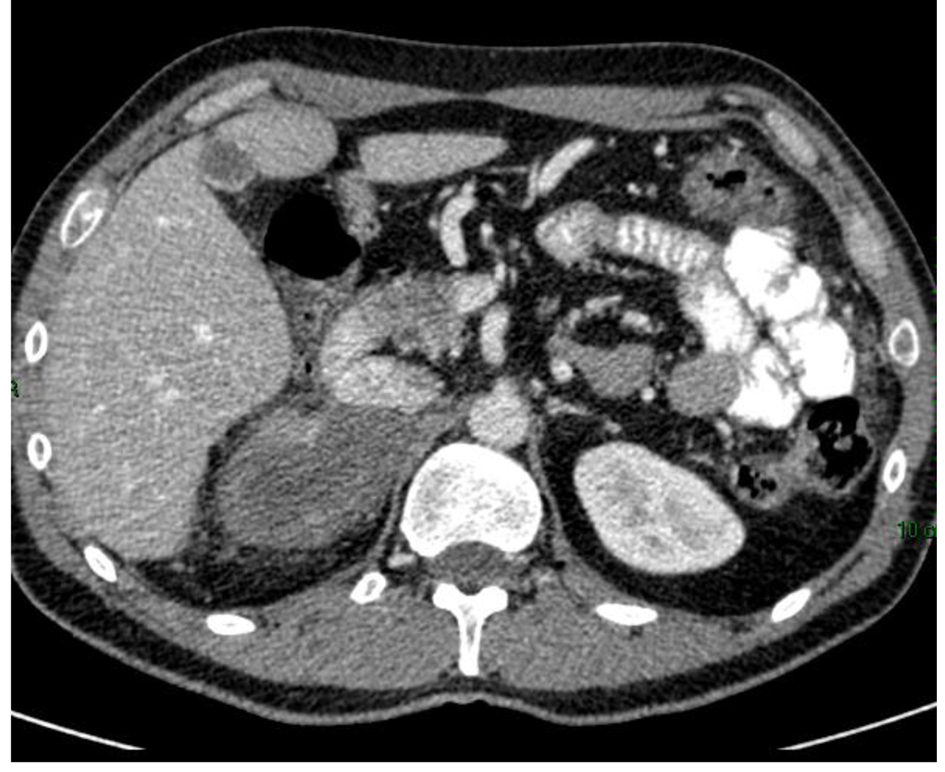

Six months after administration of mitotane, CT scan showed a reduction in size of the adrenal mass and the peritoneal metastases (Fig. 2), with a total reduction (RECIST criteria) around 40%.

![]() Click for large image | Figure 2. CT scan 6 months after mitotane treatment showing reduction in size of the adrenal mass. |